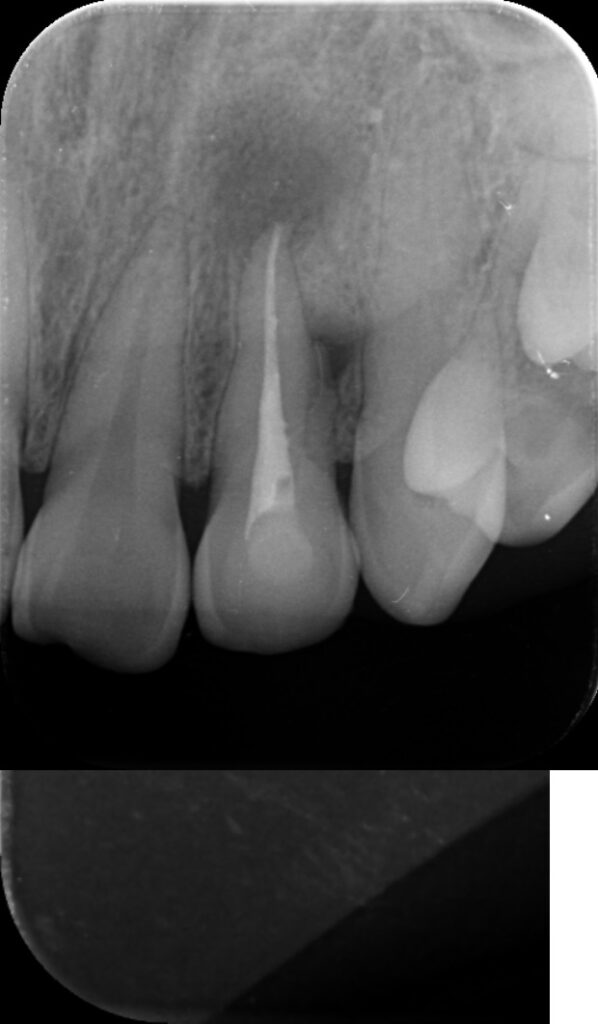

Cas très particulier d’un sillon palato-Gingival…